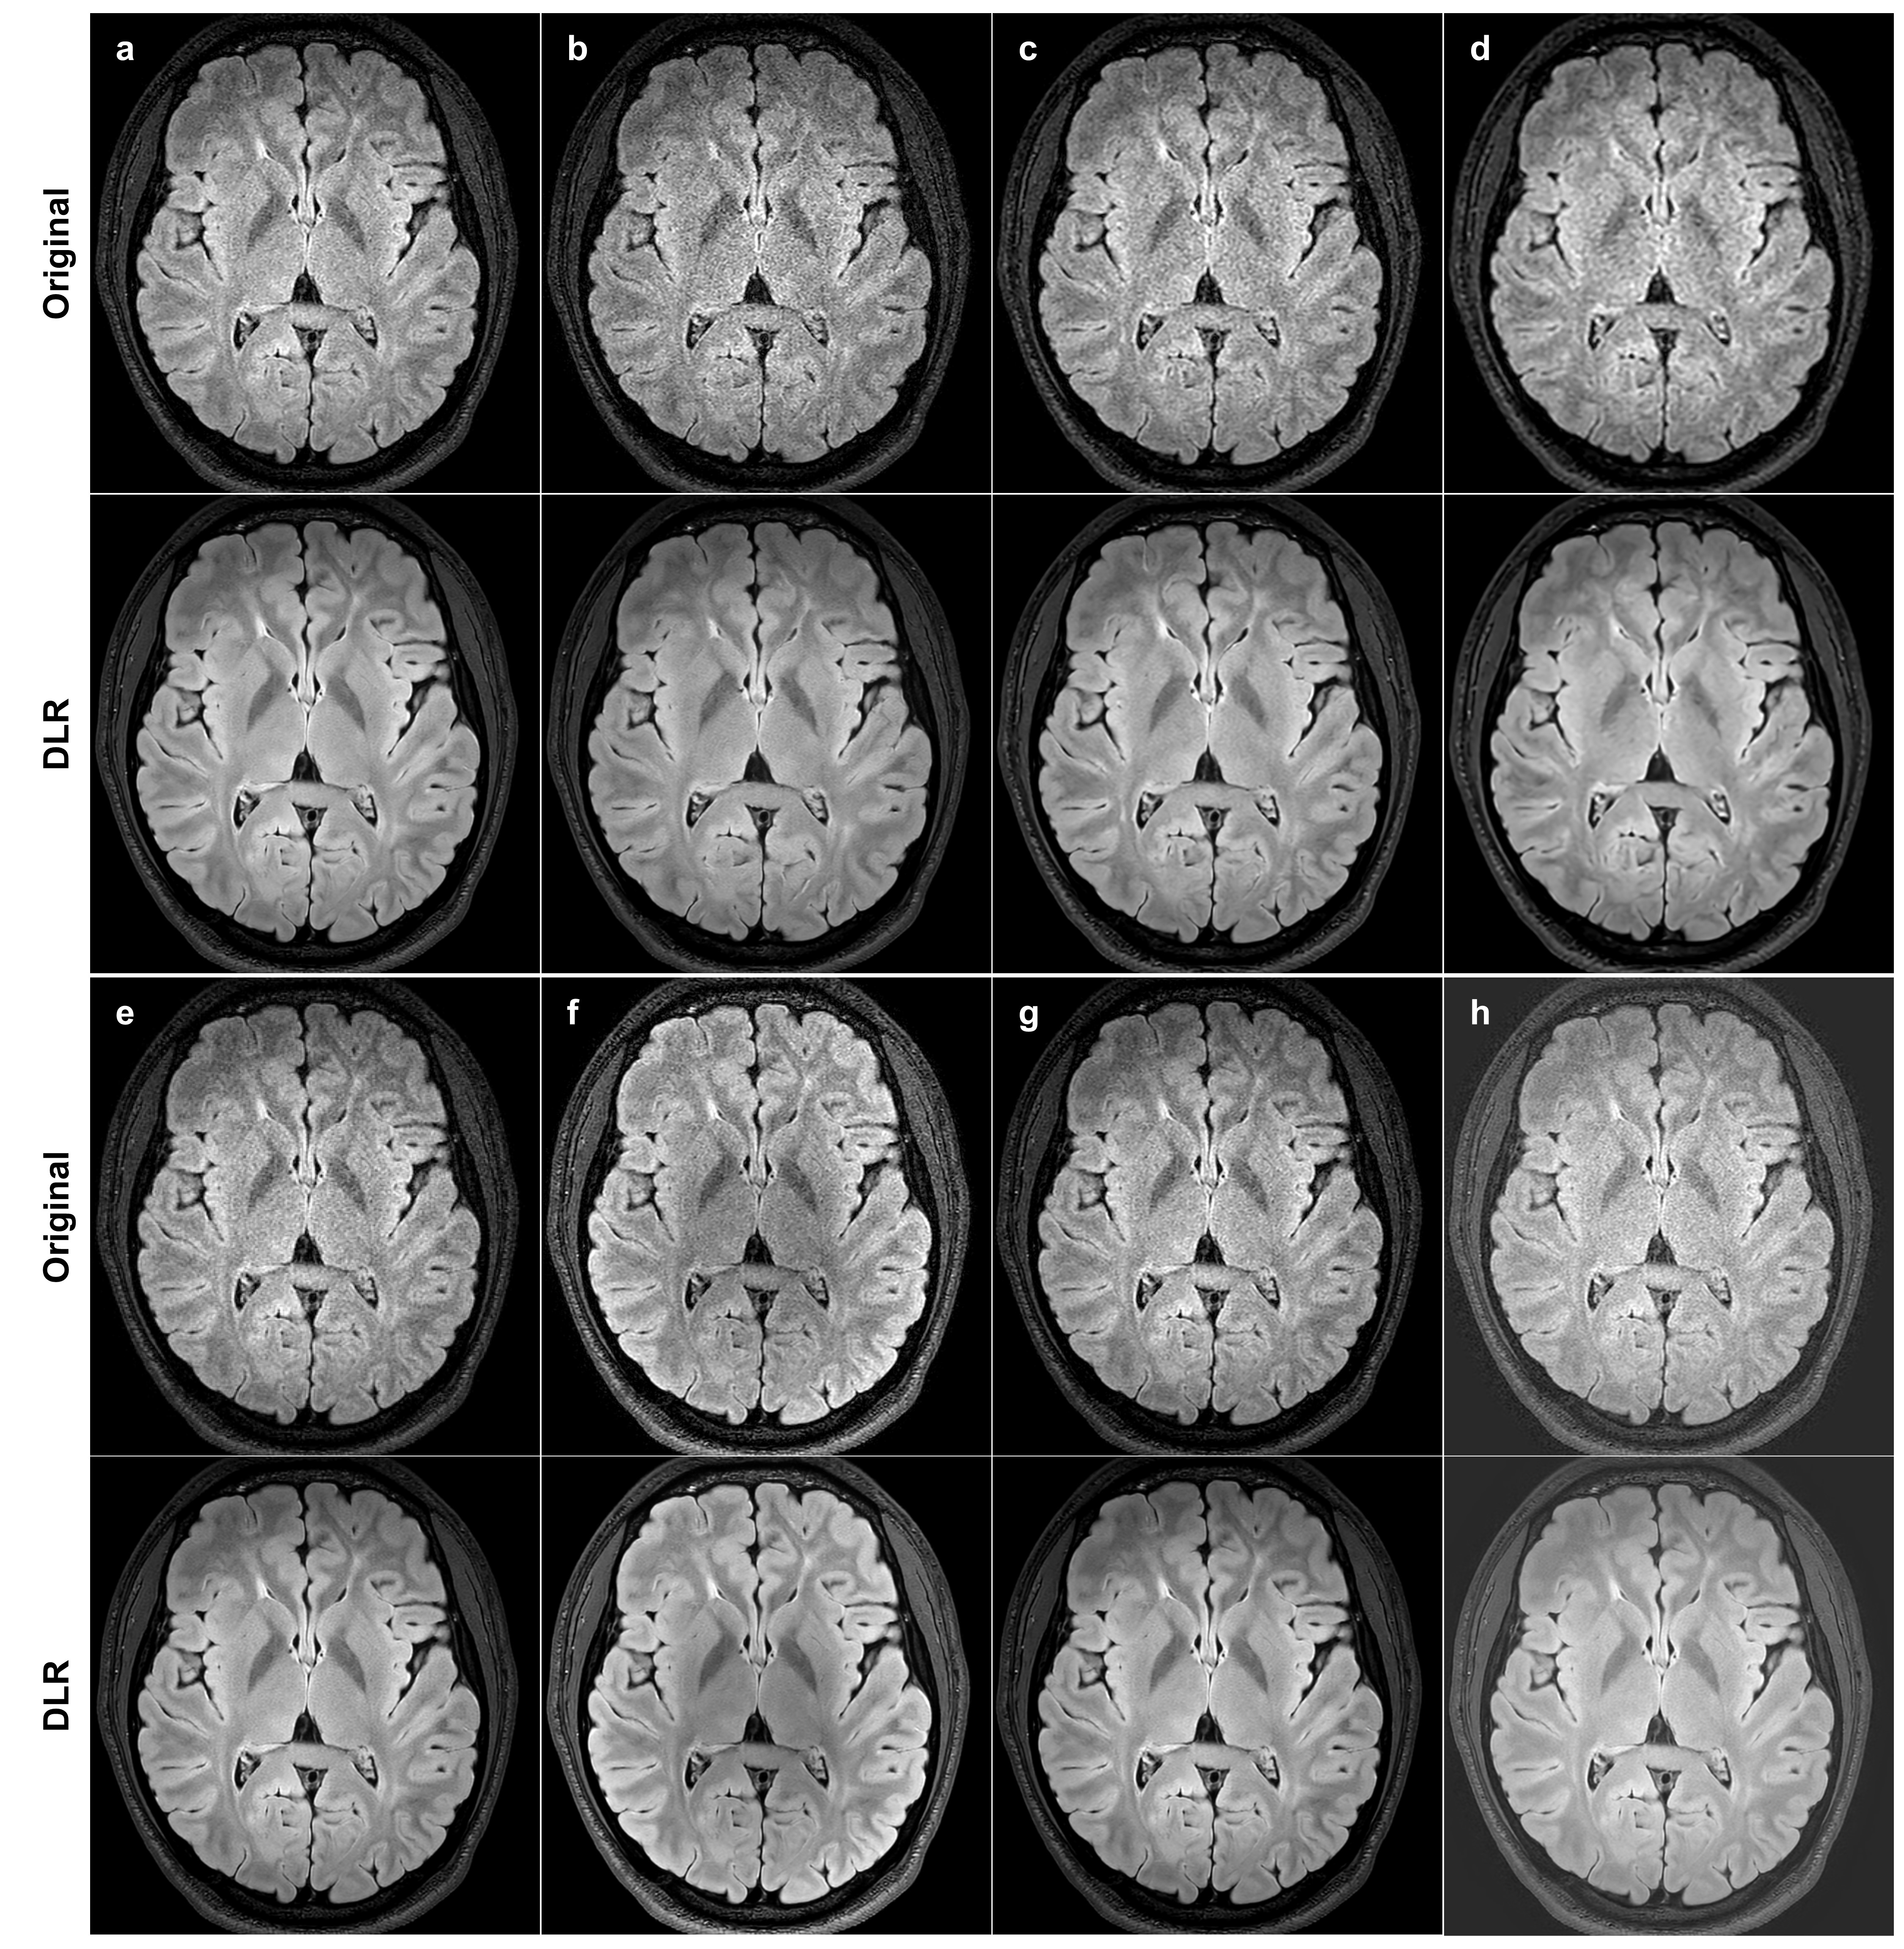

3.5 Compatibility with various scan parameter combinations

To assess the compatibility of the proposed model with diverse scan parameters that determine k𝑘k-space sampling and the reconstruction pipeline, we obtained multiple images of the same type using different sets of scan parameters. We then applied DLR to these images and performed a visual comparison between the original and DLR images. For this purpose, eight brain fluid attenuated inversion recovery (FLAIR) images were acquired using a 3D turbo spin echo (TSE) pulse sequence on a 3.0 T MR scanner (Ingenia CX, Philips Healthcare) with a 32-channel head coil. The first four images reflect variations in k𝑘k-space sampling, involving changes in SENSE factor, CS factor, elliptical sampling, acquisition voxel size, and receiver bandwidth. These images were acquired through individual scans. The remaining four images reflect variations in the reconstruction pipeline, including adjustments in in-plane interpolation factor, surface coil intensity normalization, geometric distortion correction, and complex component extraction. These images were obtained from a single scan using the scanner console’s retrospective reconstruction feature. A summary of these scan parameters is presented in Table 1. All acquired images were DL-reconstructed with a noise reduction factor of 4.0, except for those labeled CS elliptical and kmaxsubscript𝑘𝑚𝑎𝑥k_{max} bandwidth, which were DL-reconstructed with a factor of 5.0.

Figure 7 presents the original images under eight different scan parameter settings and their DLR images. The DLR images consistently exhibit lower noise and improved overall image quality compared to the original images. Notably, periventricular white matter hyperintensity remains unaffected by the DLR.

Refer to caption

Figure 7: Visual comparison between original and DLR images under various scan parameter settings. (a-d) Demonstrates variations in k𝑘k-space sampling: (a) SENSE (240s), (b) CS and elliptical sampling (182s), (c) low resolution with high receiver bandwidth (115s), and (d) even lower resolution with even higher bandwidth (67s). (e-h) Displays reconstruction pipeline variations, derived from a single scan (a) using the scanner console’s delayed reconstruction feature: (e) without in-plane interpolation, (f) with adjusted surface coil intensity normalization, (g) without geometric distortion correction, and (h) PSIR from real component extraction. DLRs across all samples significantly reduce noise and improve overall image quality, while preserving periventricular white matter hyperintensity. SENSE, sensitivity encoding; CS, compressed sensing; PSIR, phase-sensitive inversion recovery; DLR, deep learning reconstruction.